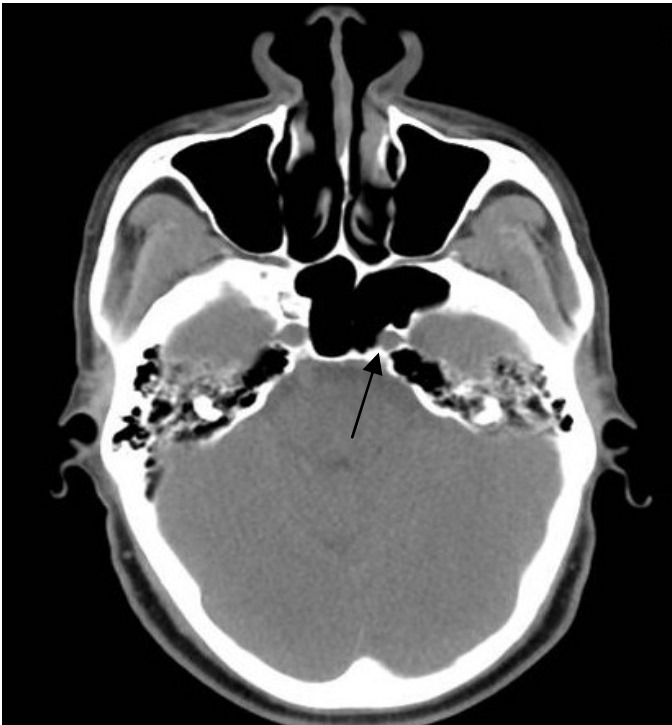

- Otorhinolaryngology